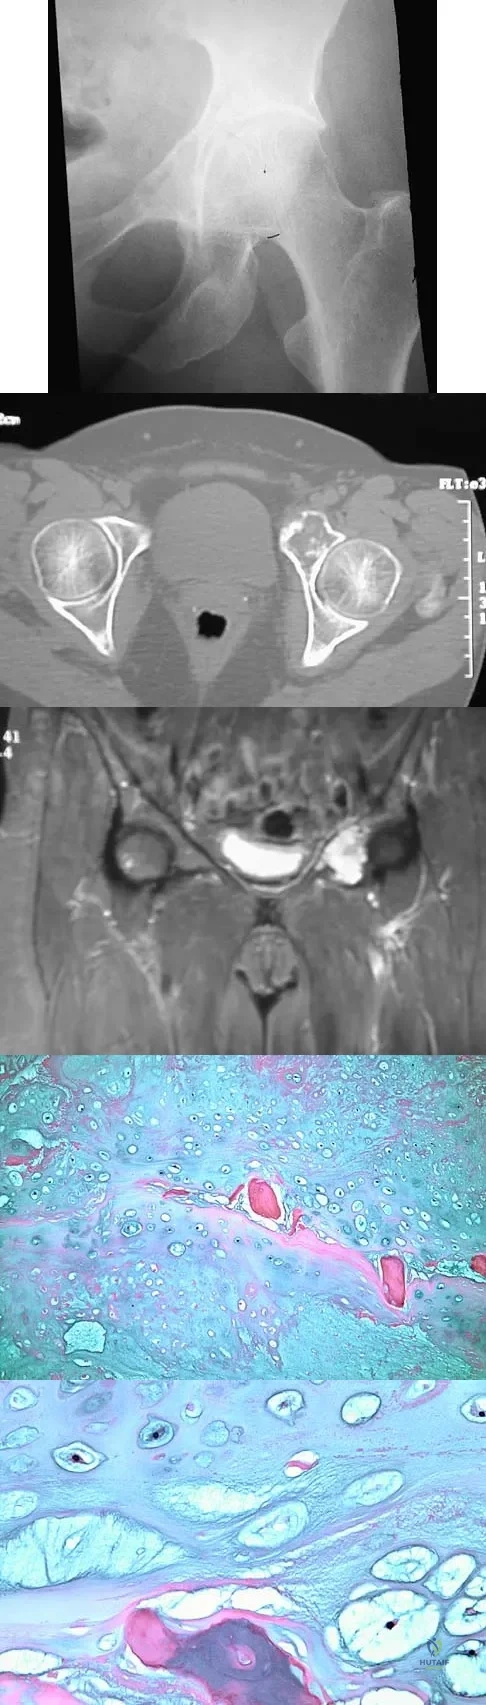

A 43-year-old woman has had pain in the left hip for the past 2 months. A radiograph, CT scan, MRI scan, and biopsy specimens are shown in Figures 16a through 16e. What is the most likely diagnosis?

Explanation

A 52-year-old man has had back pain radiating to the left leg for the past 5 weeks. A radiograph, MRI scans, and biopsy specimens are shown in Figures 23a through 23f. What is the most likely diagnosis?

Explanation